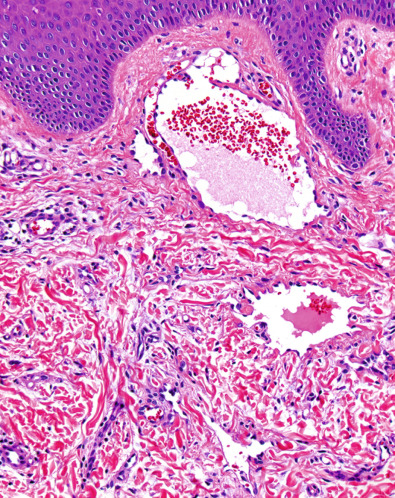

The capillary lumina are small and may be occluded by fibrin thrombi and bulging endothelial cells ( Fig. 114.3A ). In many cases, the proliferating capillaries appear to be contained within a larger, pre-existing vessel, obliterating its lumen, but sometimes the proliferation extends directly between collagen bundles ( Fig. 114.3B ). Cases associated with cryoglobulinemia typically show intraluminal and intracellular eosinophilic globules, but this finding can also be seen in the absence of cryoglobulinemia.